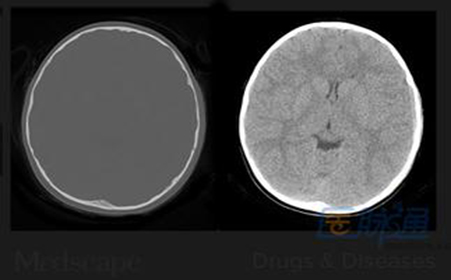

颅脑损伤对小儿智力有影响吗?